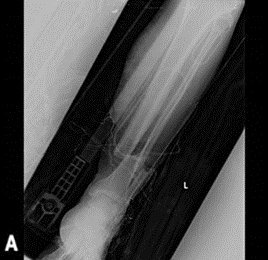

At 6 months the clinical and radiographic Follow-Up (FU) showed an exuberant callus with no signs of fracture consolidation and a bone stumps angulation in the sagittal plane. The appearance, moreover, of serum-purulent secretion from the screws of the external fixator, imposed its removal, the execution of samples for antimicrobial culture (then tested positive for Escherichia coli and taphylococcus aureus); a temporary cast was made, and the patient started a targeted antibiotic therapy for 21 days. After 15 days of wash-out from antibiotic therapy, the patient performed a new scintigraphy with marked leukocytes which showed a small cortical leukocyte accumulation in correspondence of the previous exposure area on the anterior aspect of tibial bone (Figure 4).

Figure 4: A) Scintigraphy with accumulation in the site of fracture exposure. B-C) X-rays at 6 months of follow-up. One can notice the absence of effective bone callus and an angulation at the fracture site both on B) coronal and C) sagittal planes.